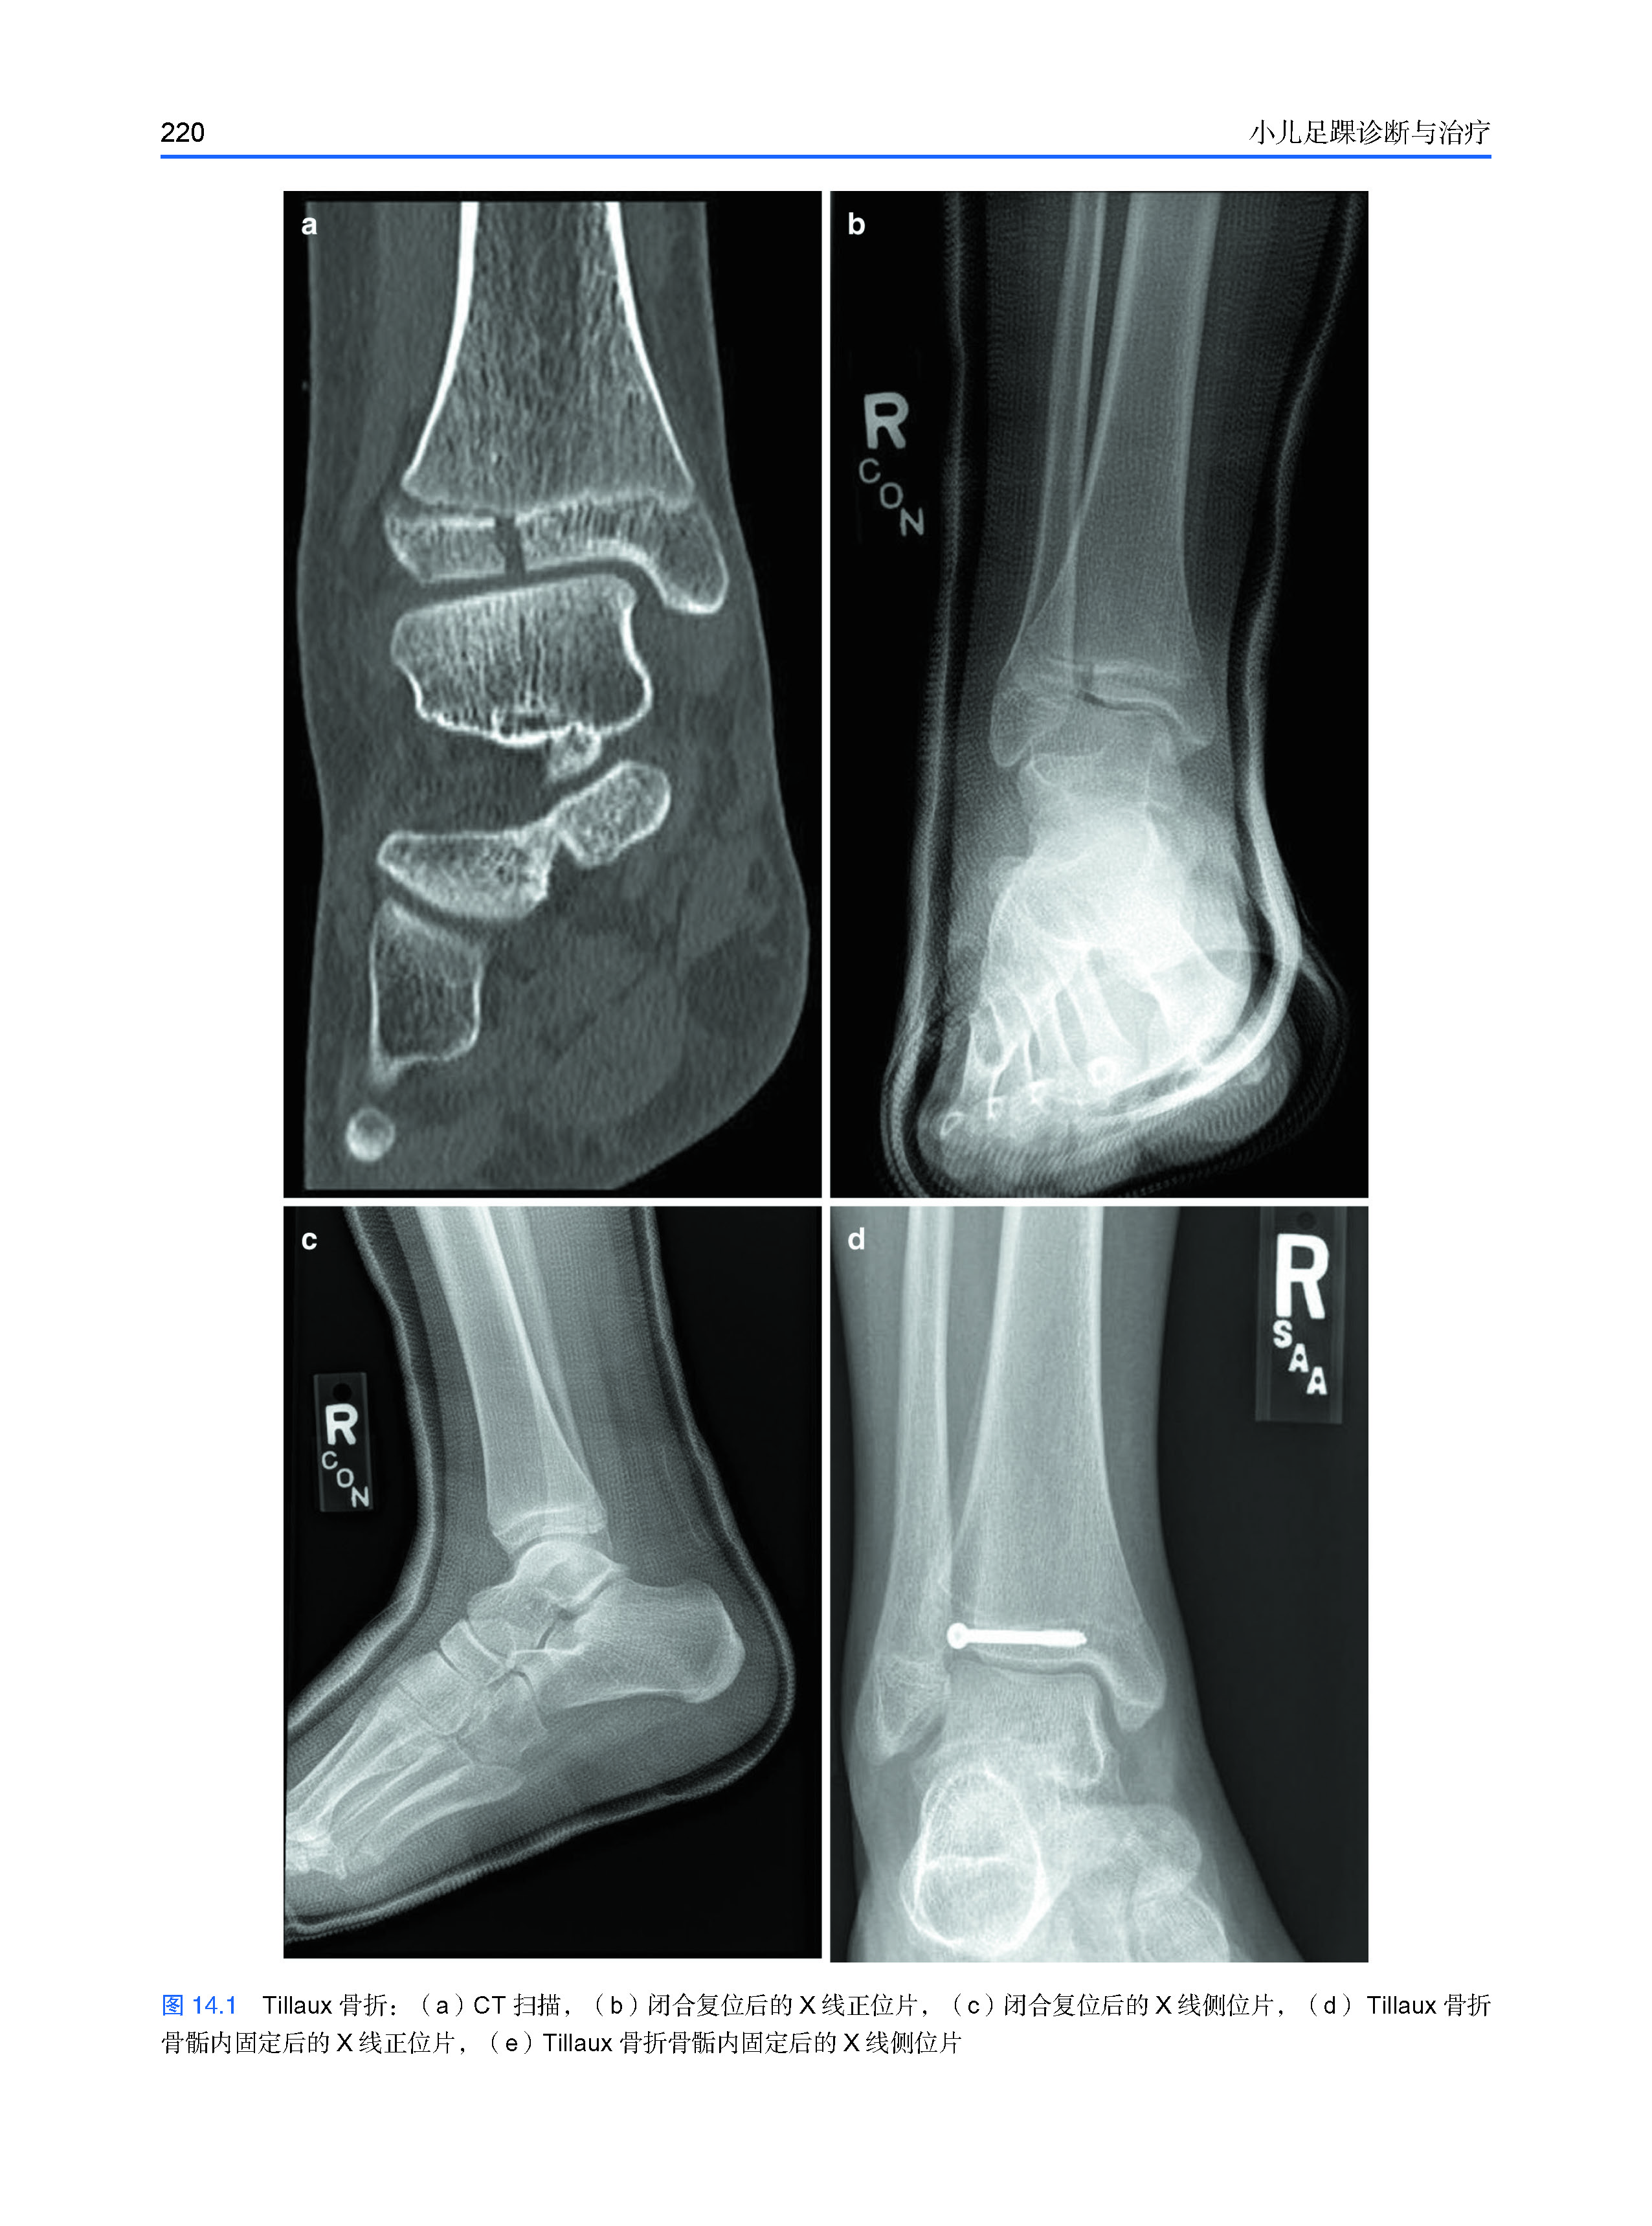

本书包括了儿童足踝的解剖特点、发育、评估和治疗。包括了临床和影像学的评估,保守治疗和手术治疗的选择,常见的足趾畸形、神经肌肉源性畸形、马蹄足、平足、运动医学及创伤等内容。